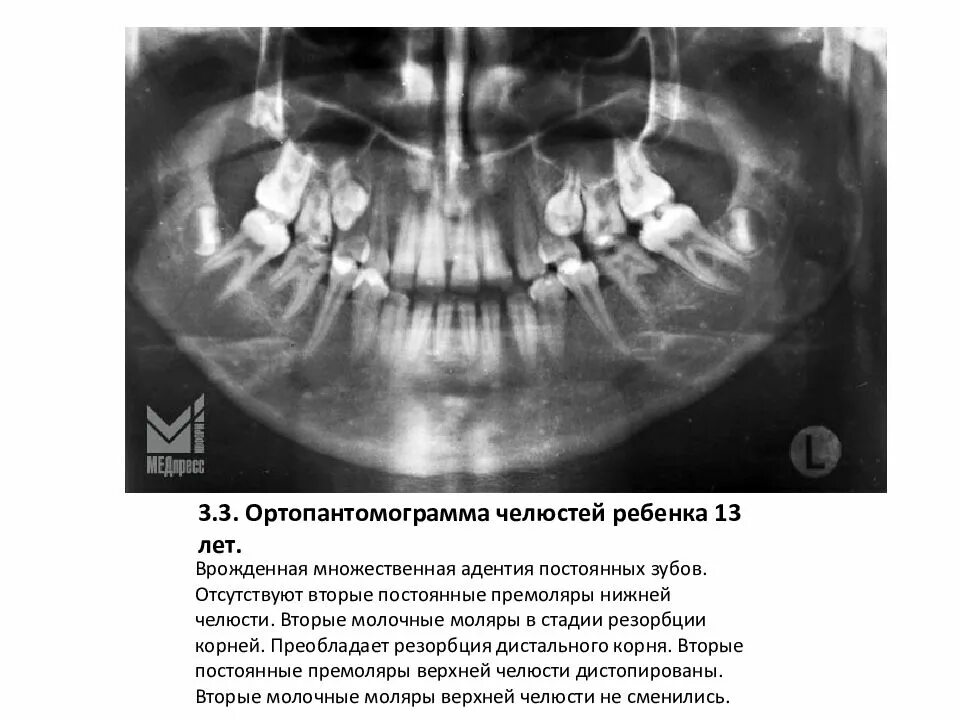

Снимок верхней и нижней челюсти